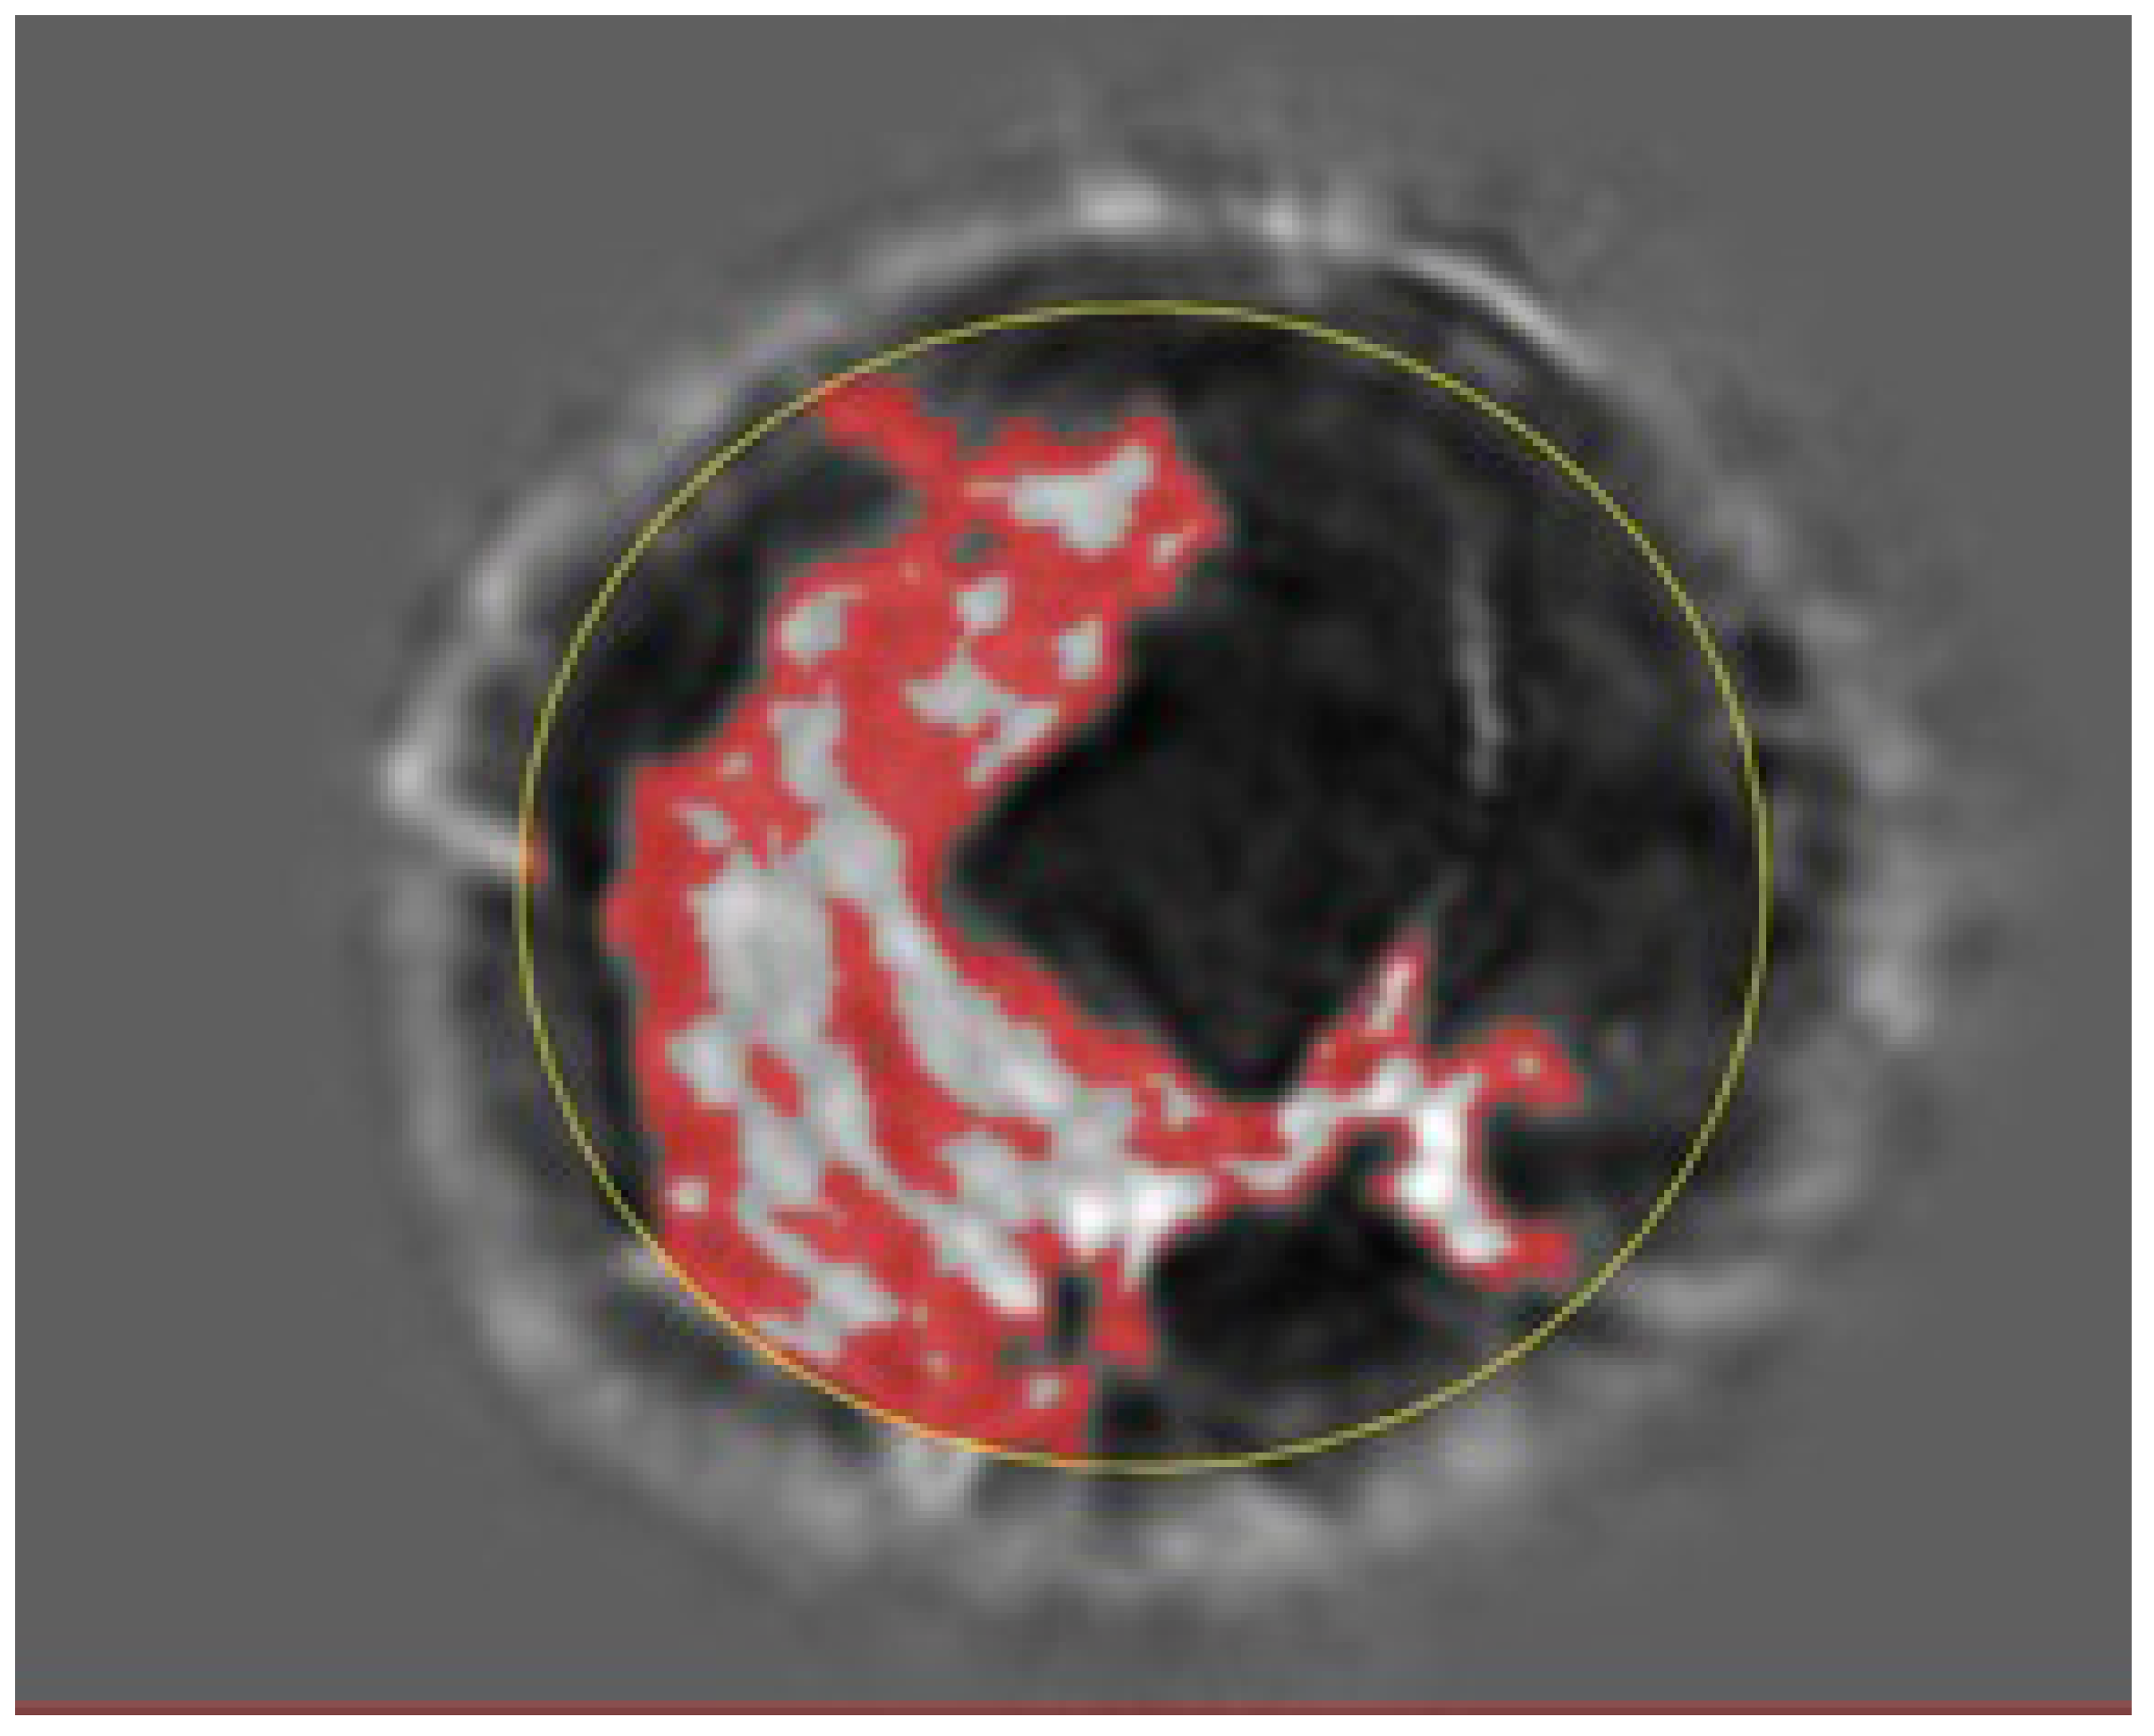

Figure 2 shows the speed of sound image of the entire FGV of a breast in axial (cranio-caudal) and sagittal (lateral) views. Figure 3 and Figure 4 show the glandular volume on day 1 of the menstrual cycle (Figure 3) and at the beginning of menstruation (Figure 4) in the same breast. These comparisons show increases in glandular volume at the onset of menstruation.

Figure 3. Glandular segmentation before menstruation. The red area is segmented glandular tissue. The lighter the grayscale, the higher the speed of sound. Ductal tissue has a higher speed of sound than glandular tissue and is shown in light grayscale outside of the red region. The yellow circle indicates the constraining ellipsoid for the segmentation (also in Figure 4).

Figure 4. Glandular segmentation on day 1 of menstruation in the same breast as in Figure 3 showing an increase in glandular volume. The red area is segmented glandular tissue only. As above, the light gray region represents a higher speed of sound ductal tissue, and the darker region shows fat.